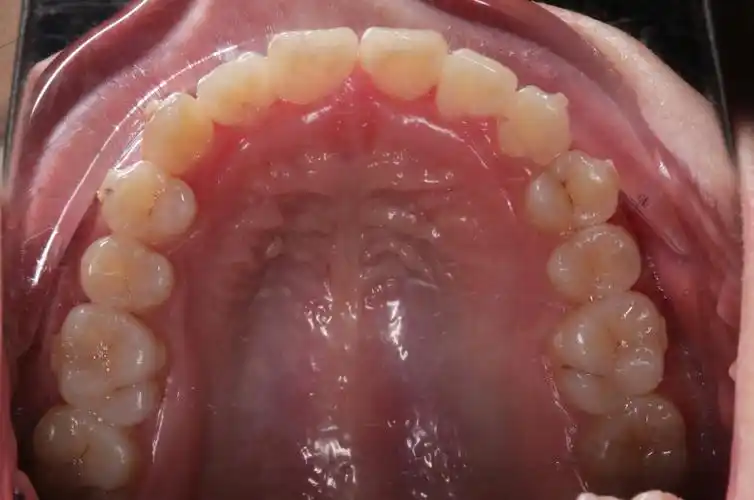

口腔医生须知资料收集正畸患者摄影资料的采集